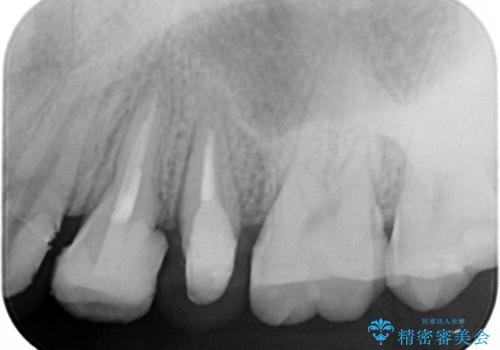

- 歯ぐきの腫れや、歯の内部が黒く見えることからの虫歯の治療を求めて来院されました。

虫歯が大きかったことから、神経の温存はできたものの歯ぐきよりも深い虫歯の問題を解決するため、部分矯正治療を併用したセラミック治療を行うこととしました。

当初、歯ぐきよりも深い虫歯の存在や、歯のポジションに問題がありましたがマルチブラケットを用いた部分矯正で行うことで歯の挺出同時に適切な位置へと歯を移動させ、歯周環境を整えたセラミック治療を行うことができました。